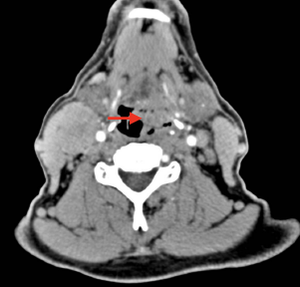

A 57-year-old man with a heavy smoking and alcohol consumption history, but no comorbidities, presented with pharyngeal pain to his primary care physician’s office. He received empirical treatment with oral antibiotics and experienced partial improvement. A couple of months later, he developed a left cervical mass with progressive growth. A head and neck CT scan revealed a hypopharyngeal tumor. Results of a tumor biopsy indicated an ulcerated, moderately differentiated squamous cell carcinoma (SCC) with lymphovascular invasion. The patient was sent to our institution for treatment.